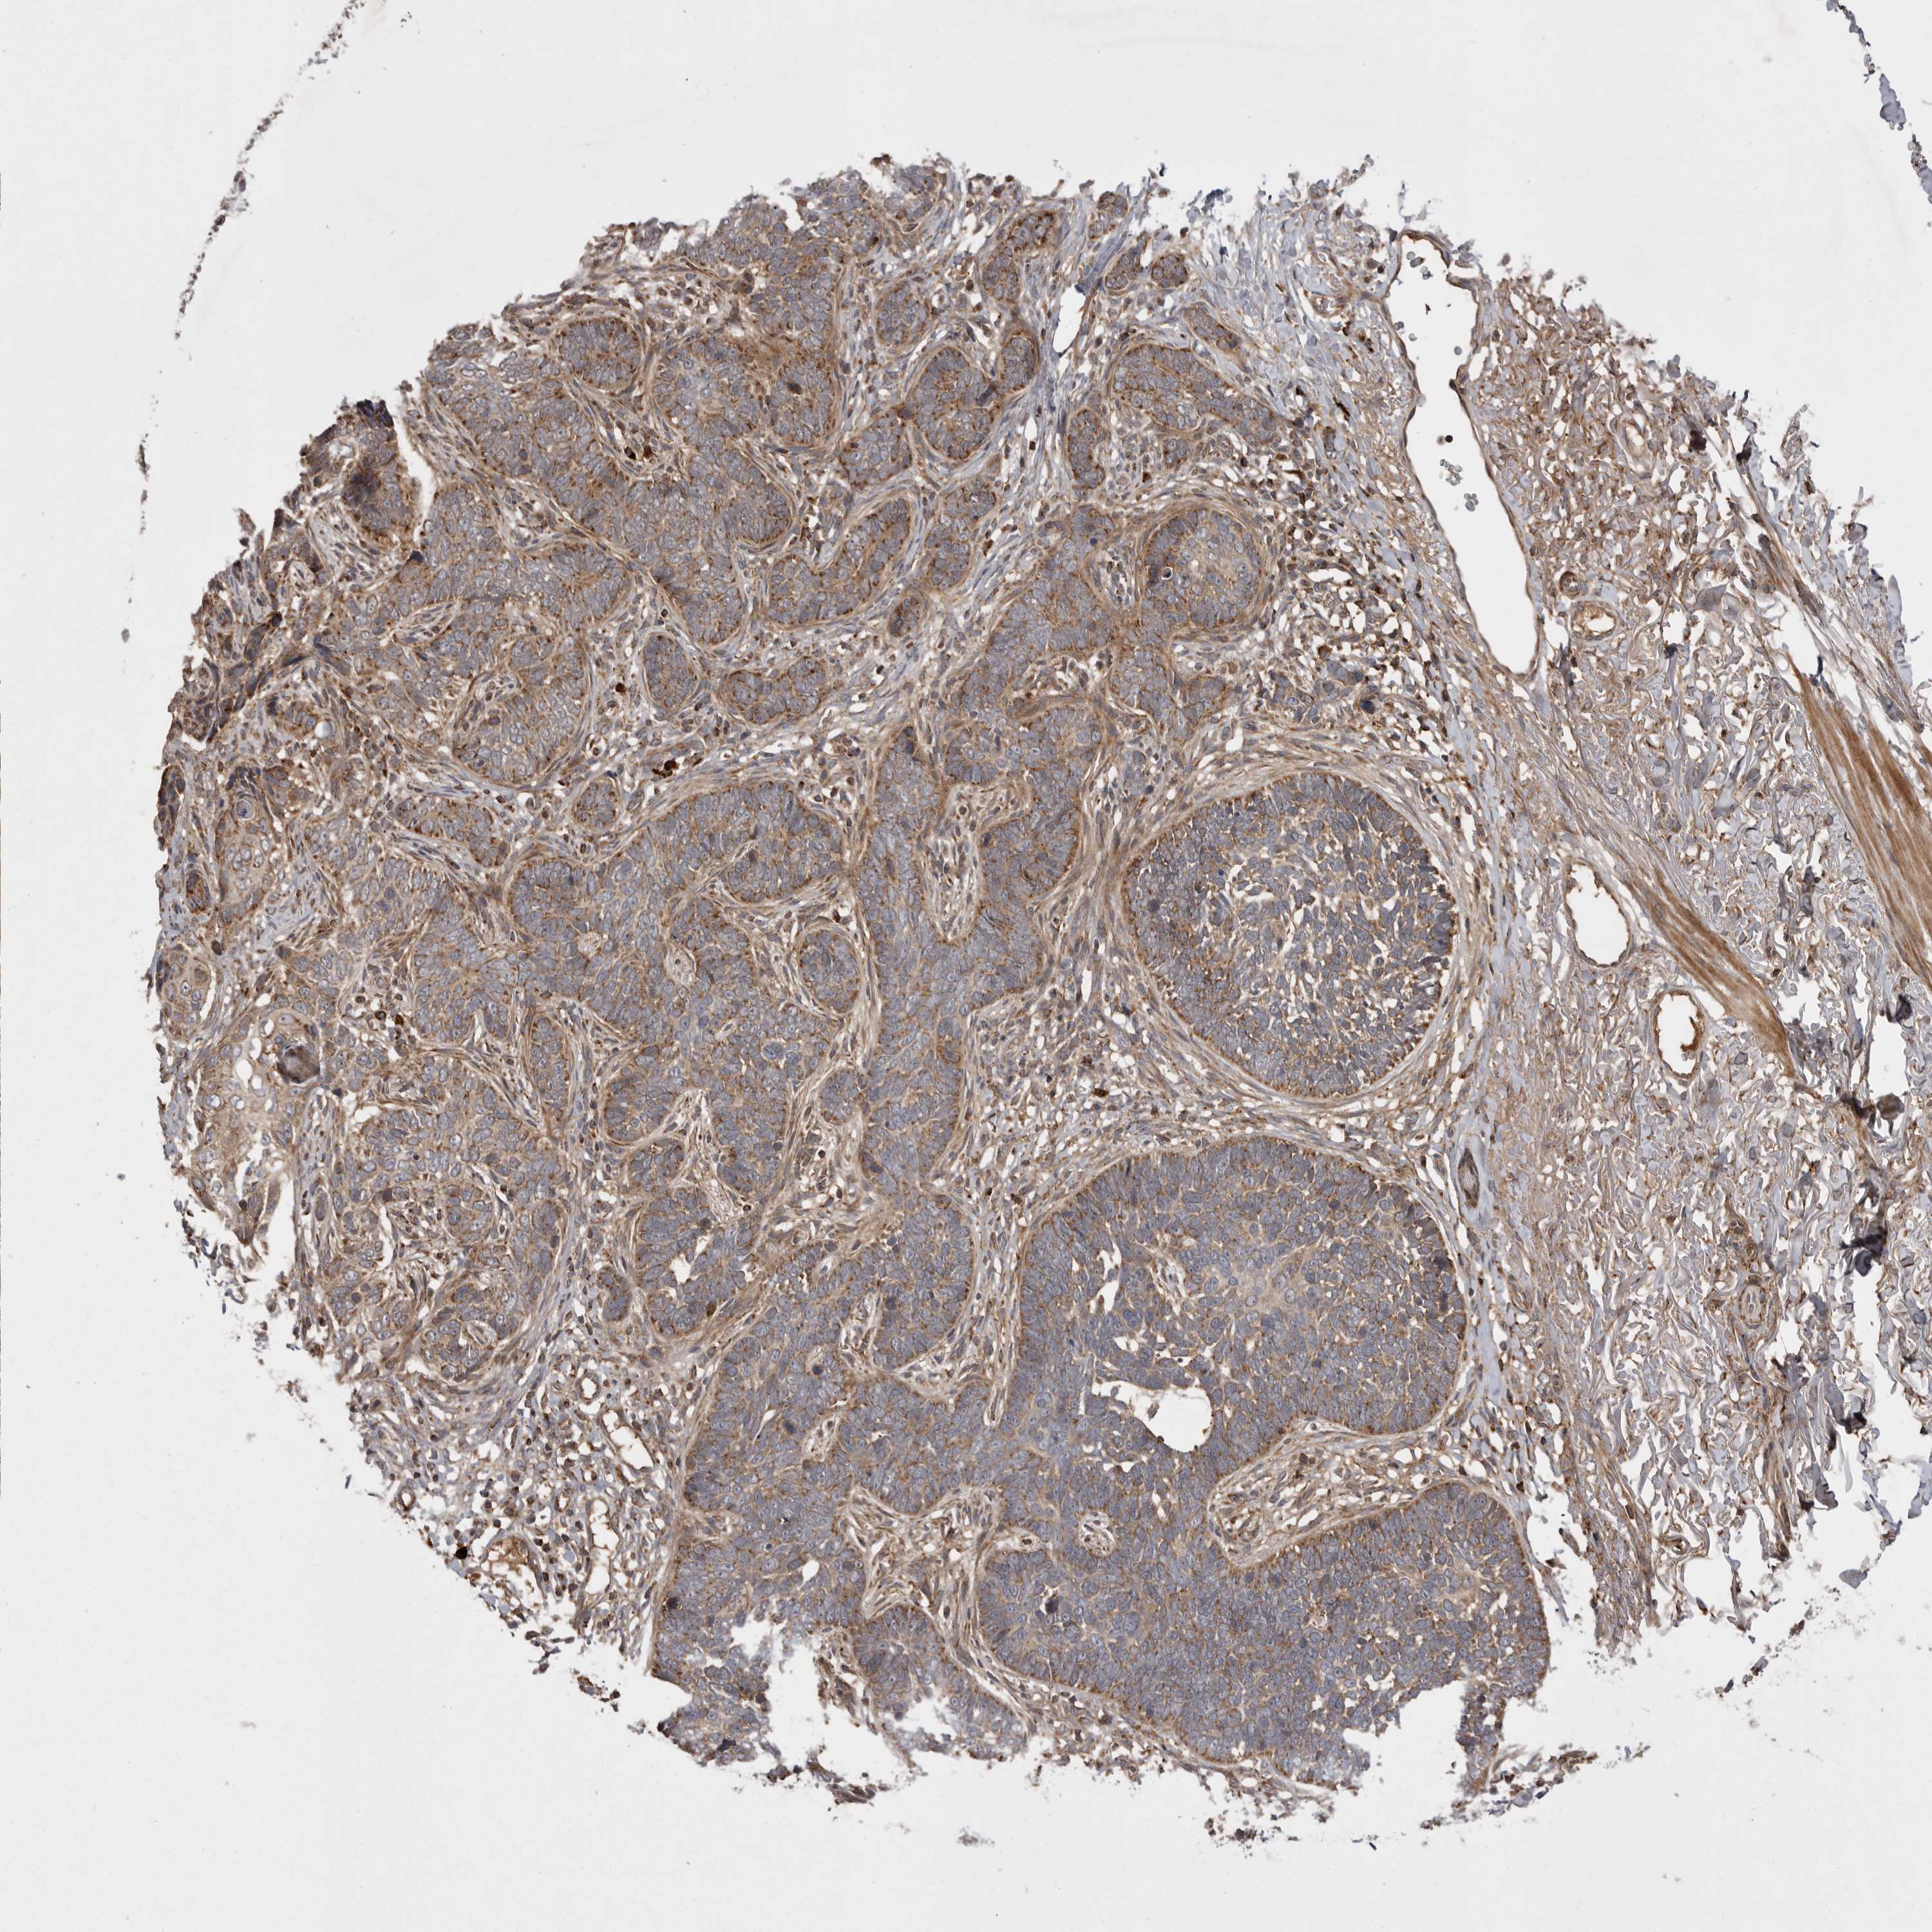

SKIN CANCER - Protein expressioni

A mouse-over function shows sample information and annotation data. Click on an image to view it in a full screen mode. Samples can be filtered based on level of antibody staining by selecting one or several of the following categories: high, medium, low and not detected. The assay and annotation is described here.

Antibody stainingi

Antibody staining in the annotated cell types in the current human tissue is reported as not detected, low, medium, or high, based on conventional immunohistochemistry profiling in selected tissues. This score is based on the combination of the staining intensity and fraction of stained cells.

Each image is clickable and will lead to virtual microscopy that enables deeper exploration of all samples and also displays staining intensity scores, fraction scores and subcellular localization as well as patient and tissue information for each sample.

Antibody HPA027168

Squamous cell carcinoma, NOS